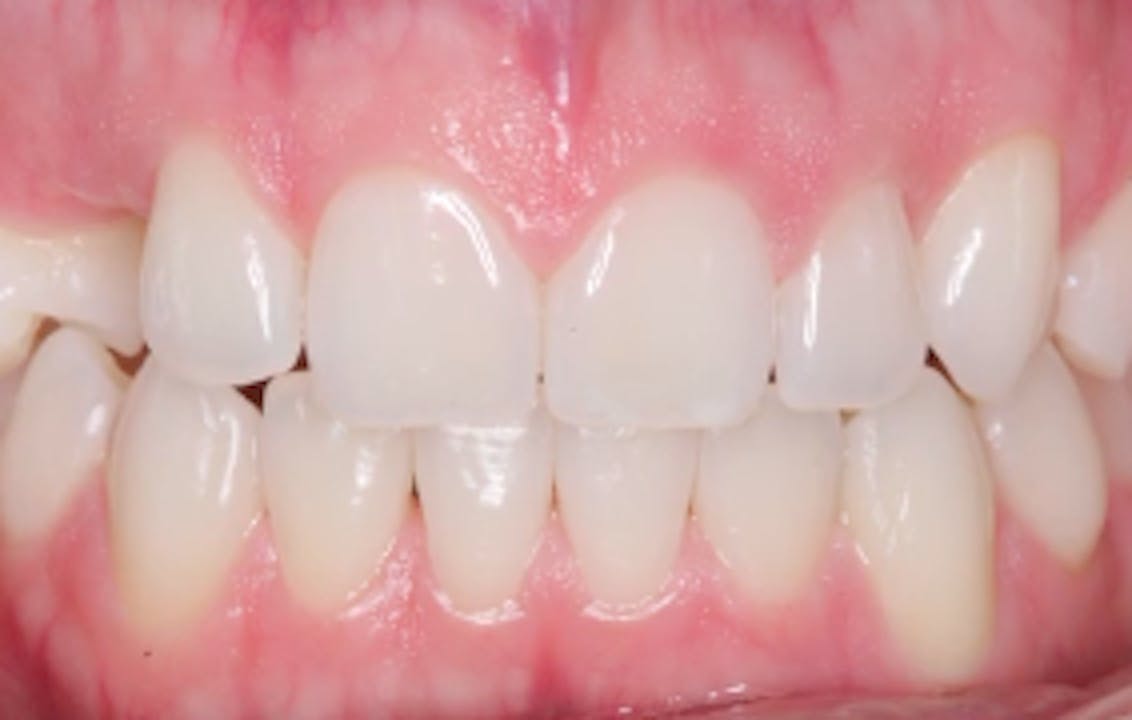

Before / After GIDE Dental Implant Center Gide Dental Reviews Gide dental institute, los angeles, california. 31,762 likes · 74 talking about this · 887 were. Find reviews, ratings, directions, business hours, and book appointments online. Dive deep (at your own pace) in a comprehensive online master class or residency with topics covering implant dentistry, esthetic dentistry,. • 550+ clinical videos on web and app • new dental videos added.. Gide Dental Reviews.

Before / After GIDE Dental Implant Center Gide Dental Reviews Premiere provider of online dental education. Learn from the world's most trusted faculty and advance your skills with gide. Find reviews, ratings, directions, business hours, and book appointments online. Clinical videos, expert interviews, live broadcasts over. Gide dental | 280 followers on linkedin. • 550+ clinical videos on web and app • new dental videos added. Dive deep (at your. Gide Dental Reviews.